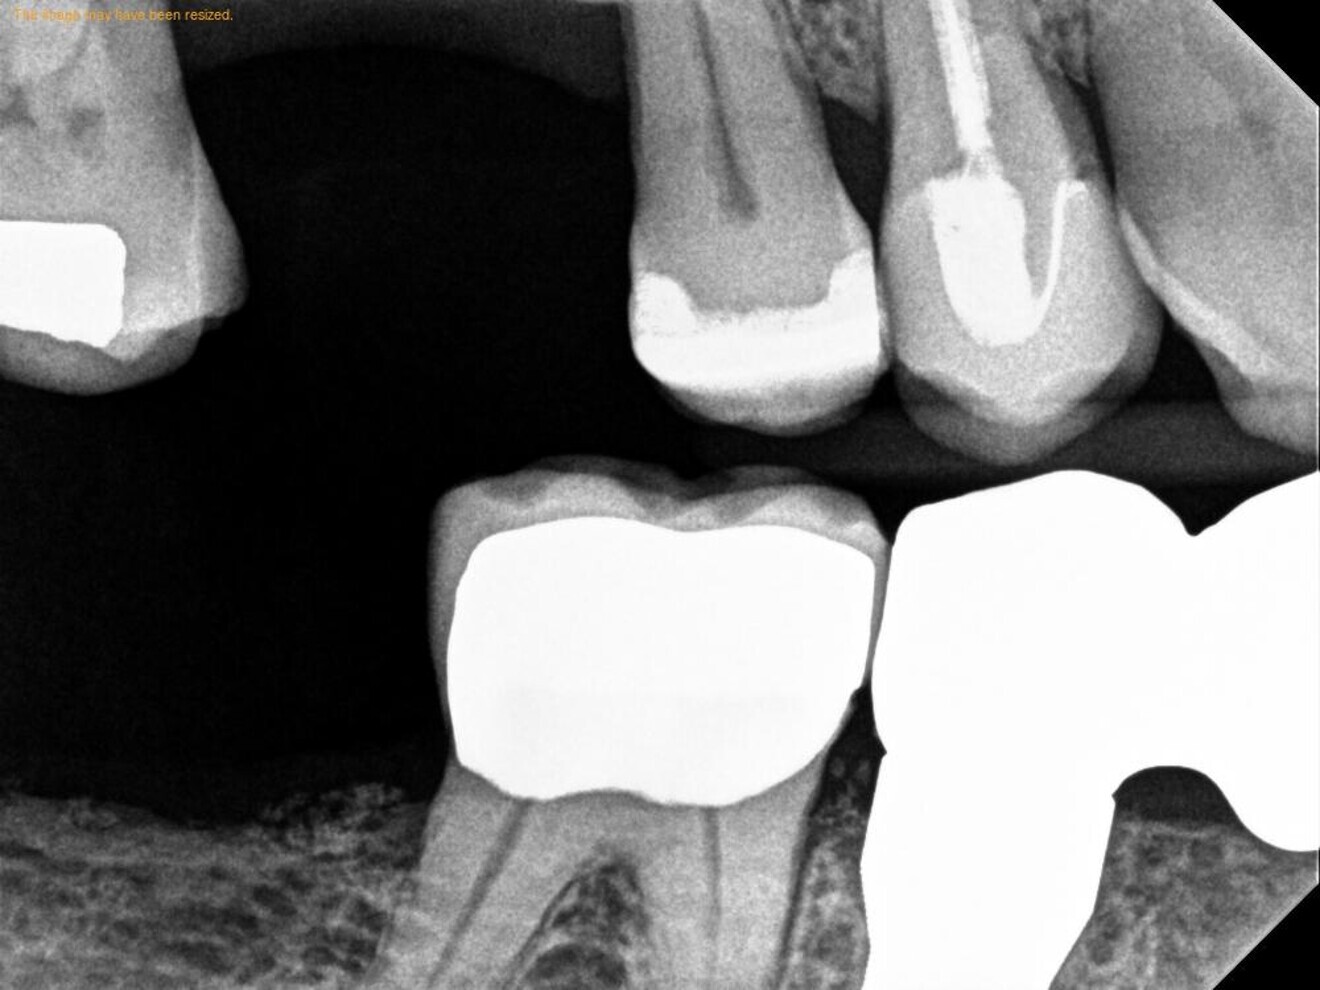

Figs. 2a–c: CBCT scan showing the failing endodontically treated tooth with an abscess.